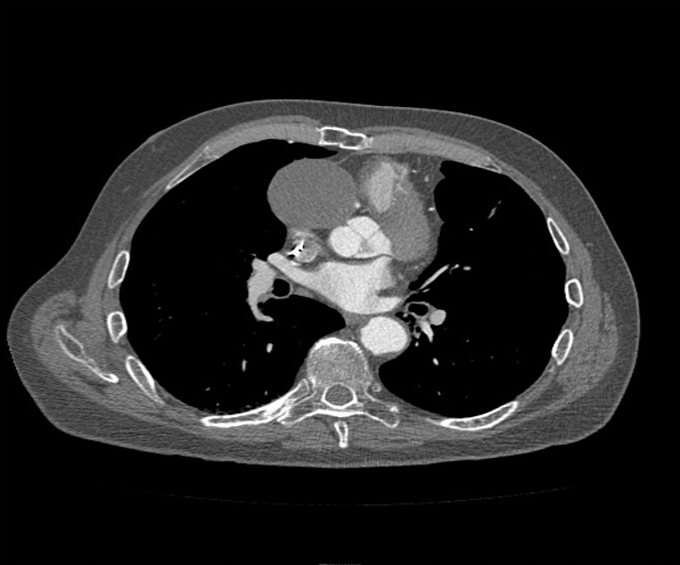

In 2019 during the patient’s surveillance with computed tomography (CT) for AAA and thoracic aortic aneurysm (TAA), an aneurysm measuring 5.4 × 5.2 cm was found on the CT (Figure 1). This aneurysm was thought to be the aneurysm found during the NSTEMI in 2015 and had progressively increased in size. As a result, the patient was referred to cardiac surgery. However, due to his prior sternotomy, ongoing tobacco use, emphysema, low ejection fraction, and a patent LIMA, the patient was not considered a good surgical candidate. He was returned to the cardiologist and after careful discussion, the heart team decided to proceed with a transcatheter exclusion of his SVG aneurysm.

Figure 1

Figure 1. Surveillance computed tomography taken for thoracic aortic aneurysm; the brighter area shows blood flow into the aneurysm.